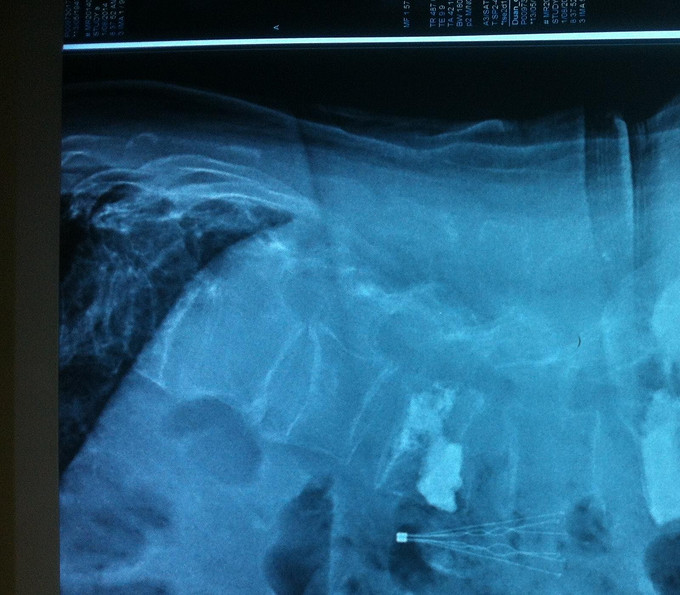

诊断:腰椎骨折 骨质疏松症 处理: 1、完善相关辅助检查,明确诊断,有无手术指证; 2、完善手术评估,有无手术禁忌,手术风险及并发症; 3、在局麻下行腰椎骨折椎体pkp术 4、术后给予全身抗骨质疏松治疗

随访 1、术后患者腰部疼痛明显减轻,术后第3日带支具下地活动,腰部轻度疼痛。 2、术后1个月,患者腰部无明显疼痛,腰部活动良好。 讨论:1、老年轻度外伤后出现腰痛,应行腰椎MR检查明确有无压缩性骨折? 2、老年骨质疏松骨质手术后是否常规抗骨质疏松治疗